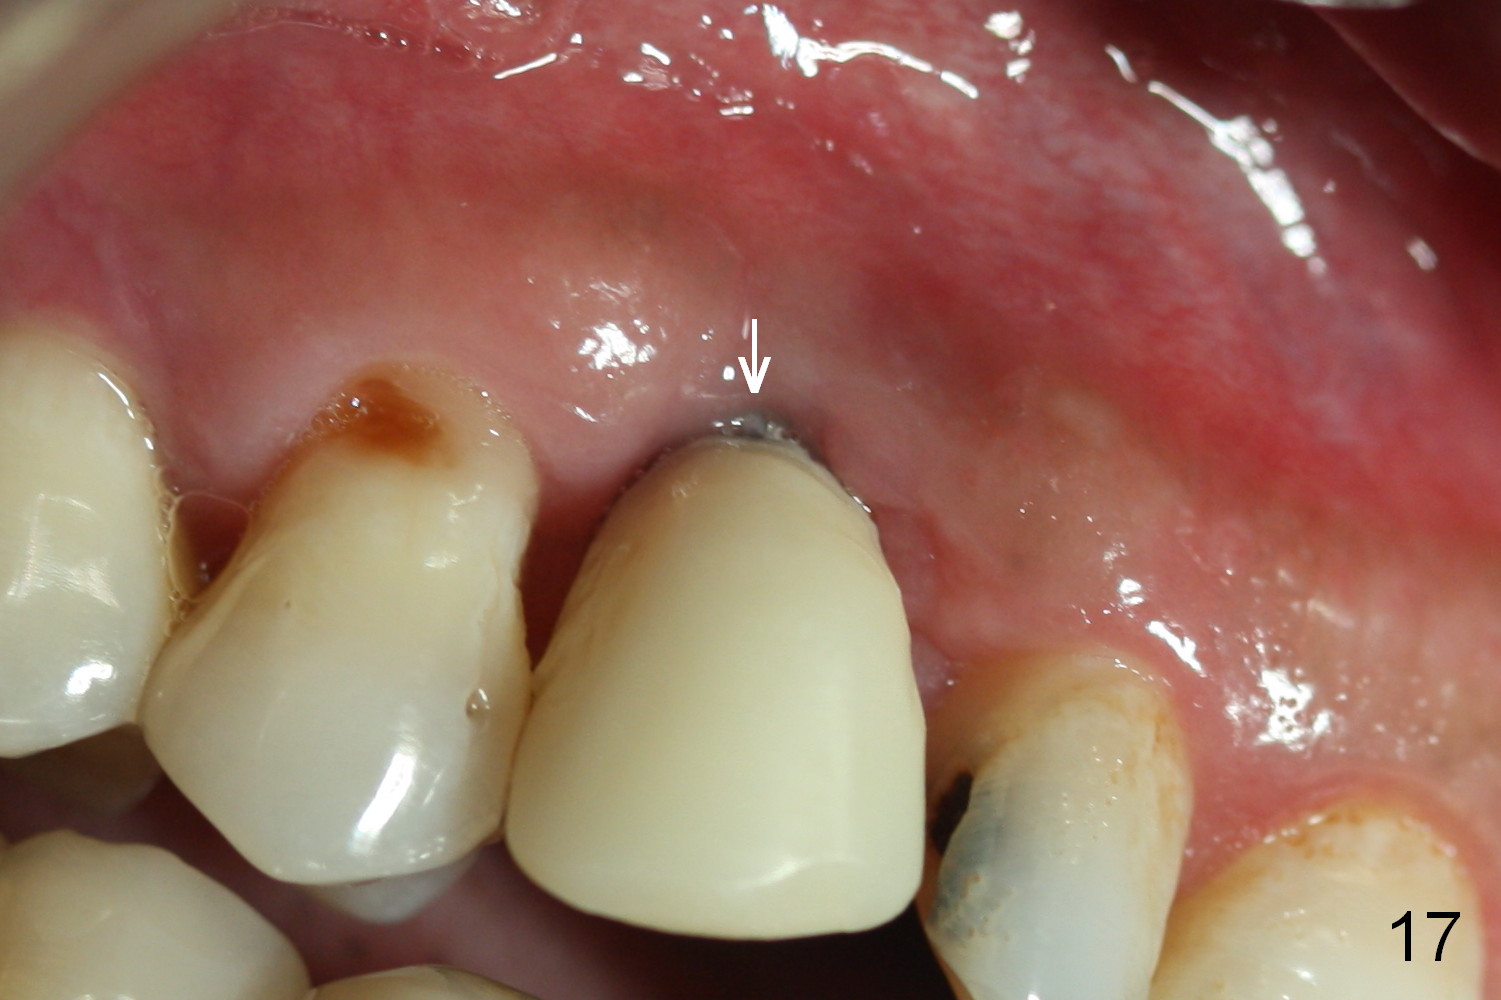

One and a half months later (3 months postop), the patient returns for final crown impression. The buccal gingiva has grown coronally (Fig.17 arrow). The implant appears to have osteointegrated (Fig.18). The buccal plate has become concave (Fig.19 arrowheads). To maintain the gingival level, the buccal portion of the implant/abutment (Fig.19 *) is going to be reduced (Fig.20 *). The margin of the definitive restoration will be at the prep margin and thin so that the gingiva is expected to continue to be growing coronally after cementation.